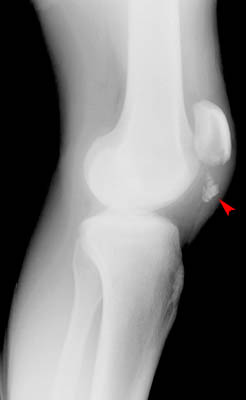

Transverse Avulsion Patellar Fracture

| In the image shown below, the distal portion of the patella was avulsed. |

Lateral view of knee |